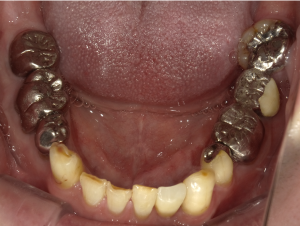

50代 インプラント治療(右上3左上3のみGBR)

| 年代・性別 | 50代・男性 |

| 主訴 | 入れ歯が合わず毎日ヨーグルトしか食べることができないので、しっかり咬めるインプラントにしたい。 |

| 部位 | 右下⑦⑥5④ 上顎③2①①2③ 左下67 |

| 治療期間 | 約9ヶ月 |

| 費用 | ¥4,273,500(税込) |

| 副作用・リスク |

|